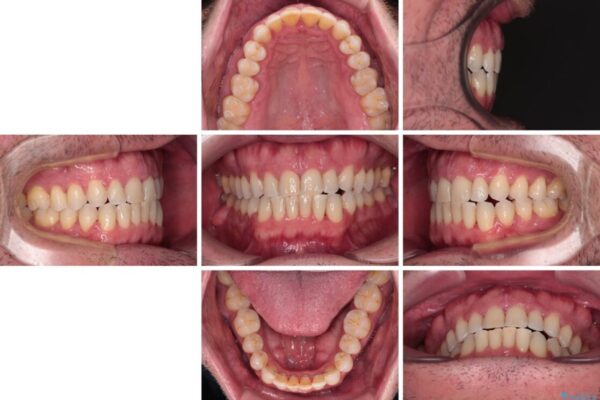

治療後

• 前歯でものを噛みきりたい 目立たない装置でのワイヤー矯正 治療後画像